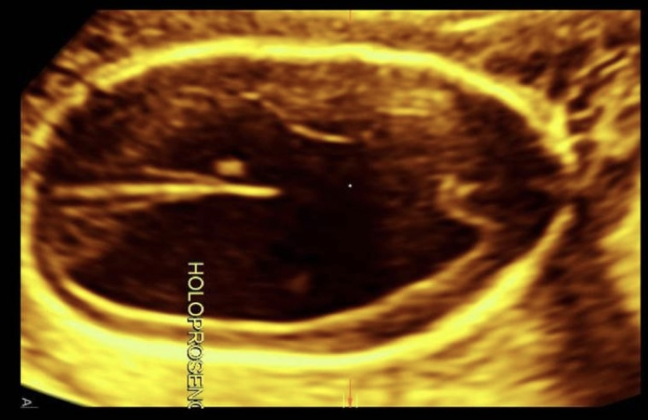

absent cavum septum pellucidum + septop-optic dysplasia are common findings in

.

a) dandy walker malformation + lissencephaly

b) cerebellar agenesis + dandy walker malformation

c) holoprosencephaly + schizencephaly

d) holoprosencephaly + dandy walker malformation

septo-optic dysplasia = mild form of lobar holoprosencephaly

* absent cavum septum pellucidum + optic nerve hypoplasia